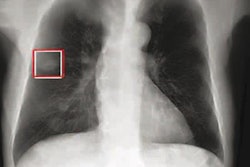

Primary outcome was the detection rate of clinically significant lung nodules confirmed on CT taken within three months, where significant nodules were defined as solid nodules larger than 8 mm or subsolid nodules with a solid portion larger than 6 mm (Lung-RADS category 4). Pathologic results were reviewed four months after trial termination. Detection rate was defined as the number of true-positive x-rays divided by the total number of x-rays. Secondary outcomes included positive rate, sensitivity, false referral rate, and lung cancer detection rate.

The trial demonstrated an increased detection rate of Lung-RADS category 4 nodules in the AI-group (AI vs. non-AI-group; 0.59% [31/5,238] vs. 0.25% [13/5,238]; p = 0.008).

Chest CT was obtained between the two groups within three months. Among those who underwent chest CT, the prevalence of significant nodules was similar and the performance of chest x-ray showed increased sensitivity in the AI group. Chest x-ray for these AI group patients also showed higher positive and negative predictive values, with very few false positives.